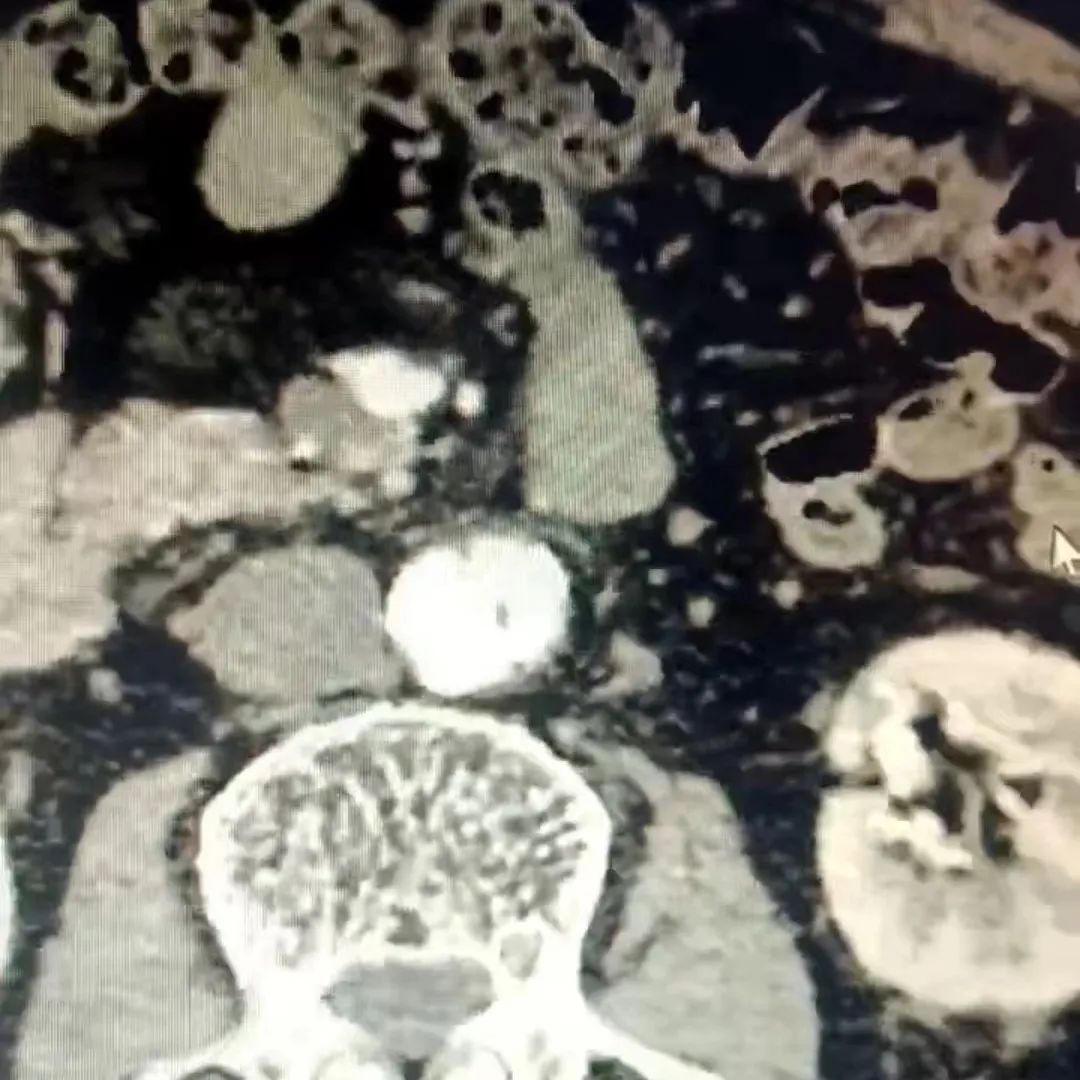

科室接诊后,在术前进行CT检查时发现卢大爷体内藏着一个“定时炸弹”——腹主动脉夹层!主动脉夹层指主动脉腔内的血液从主动脉内膜撕裂处进入主动脉中膜,使中膜分离,沿主动脉长轴方向扩展形成主动脉壁的真假两腔分离状态,若不及时处理有可能造成大动脉撕裂出血、内脏或四肢缺血,导致生命危险!

腹主动脉夹层